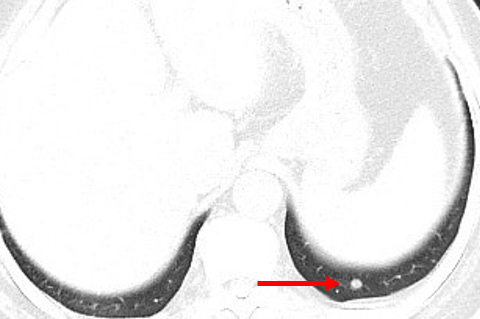

2015.09.25 CT: 双肺多发转移

2015.09.25: